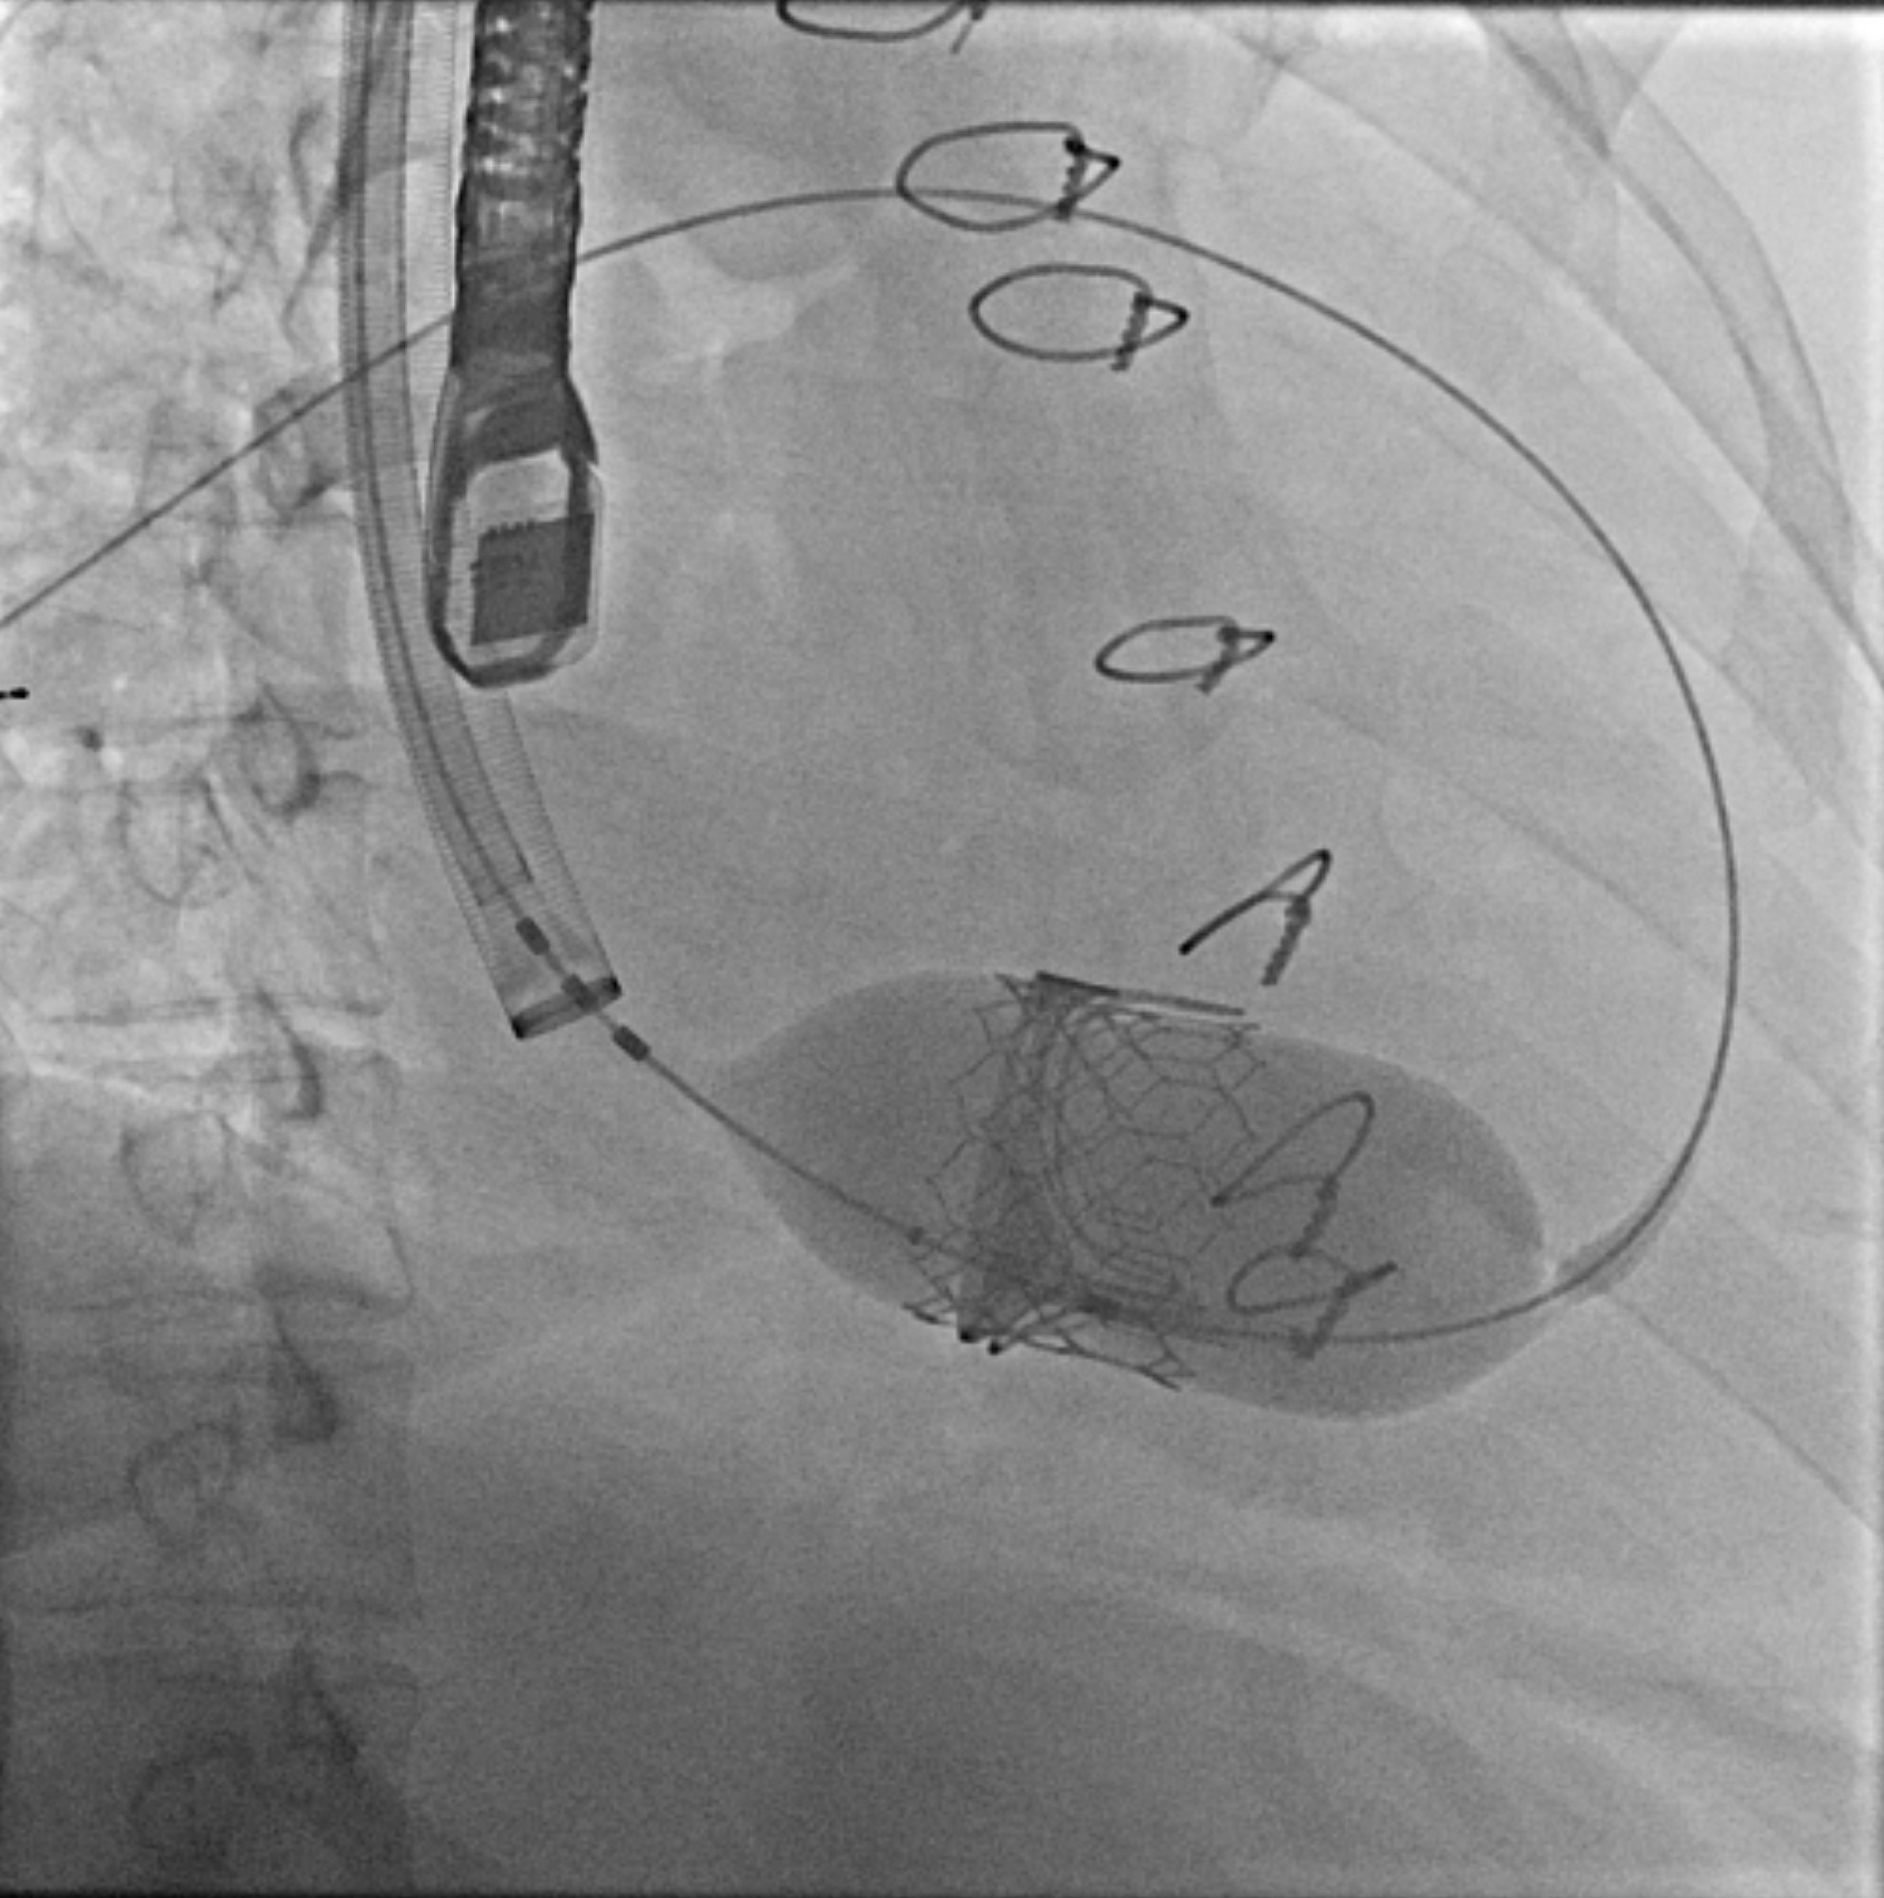

Case: A 53-year-old woman presented with acute dyspnea and orthopnea two months after a 33-mm Mitris Resilia tricuspid valve replacement for severe tricuspid regurgitation. Her history included mild aortic insufficiency and non-obstructive coronary artery disease. Transthoracic echocardiography revealed a large pericardial effusion with tamponade physiology, necessitating urgent pericardiocentesis. Transesophageal echocardiography demonstrated early SVD of the bioprosthetic valve, with poor leaflet coaptation, a central coaptation gap, and restricted anterior leaflet mobility. Extensive evaluation excluded infectious and autoimmune etiologies: blood cultures, inflammatory markers, viral serologies, thyroid function, and pericardial fluid cytology were unremarkable. Despite pericardial drainage, right atrial pressures remained elevated (mean 19 mmHg) on repeat right heart catheterization. Following a comprehensive heart team evaluation, a 29-mm Edwards Sapien valve was deployed via right internal jugular venous access within the failing surgical valve under fluoroscopic and echocardiographic guidance. Intraprocedural TEE demonstrated immediate reduction of tricuspid regurgitation severity to trace with a mean gradient of 1 mmHg. The patient had an uncomplicated recovery and was discharged the following day.

Conclusion: This case represents one of the earliest reported tricuspid bioprosthetic valve failures requiring intervention within two months of implantation. The exact mechanism of SVD remains unclear; proposed theories include non-calcific mechanisms such as early mechanical leaflet fatigue, material or manufacturing defects, or technical factors related to surgical implantation. The comprehensive negative workup supports intrinsic valve material failure rather than infectious or inflammatory processes. The successful transcatheter ViV approach demonstrates excellent technical feasibility with immediate hemodynamic improvement, confirming its role as a viable alternative to high-risk redo surgery in early valve failure.